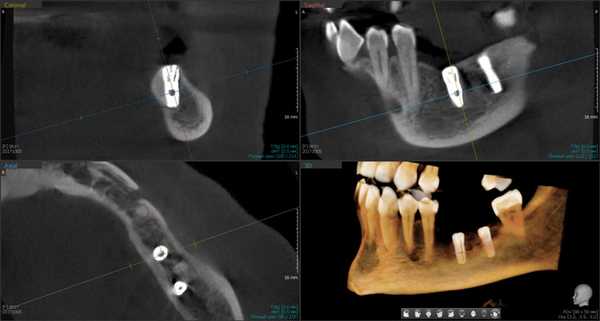

Рис. 1. Асимметричное строение нижнеальвеолярного нерва, добавочный канал в области нижней челюсти справа во фронтальной проекции конусно-лучевой компьютерной томографии от Vatech.

Лучевое обследование проводилось на различных этапах имплантации. Как правило, всем пациентам выполнялась ортопантомография на дооперационном этапе. В сложных клинических ситуациях использовались дентальная объемная томография. Изучение литературных источников по топографической анатомии лицевого скелета показало отсутствие какой-либо информации о связи строения и расположения нижнечелюстного канала с вероятностью повреждения нерва при установке имплантатов. Результаты проведенных собственных рентгеноанатомических исследований челюстно-лицевой системы позволили выделить клинически значимые особенности строения и расположения нижнечелюстного канала и нерва в теле челюсти. В этой связи к предрасполагающим анатомическим факторам риска развития хирургических осложнений при дентальной имплантации могут быть отнесены:

Первая - легкая степень обусловливалась сдавлением ствола за счет отека, гематомы или прямой, непосредственной, но незначительной компрессией имплантатом. Рентгенологическое исследование посредством конусно-лучевой компьютерной томографии и программного обеспечения Ez3D-iV4.3.0 от Vatech, при маркировке нижнечелюстного канала, установило расположение дентальных имплантатов непосредственно у нижнечелюстного канала или эндопротезы перфорировали верхнюю стенку канала (Рис.2). Тактика лечения такого вида патологии основывается на сохранении имплантатов, назначении витаминов группы В, средств, оказывающих непосредственное стимулирующее влияние на проведение импульса по нервным волокнам, усиливающих сократимость гладкомышечной мускулатуры под влиянием агонистов ацетилхолиновых, адреналиновых, серотониновых, гистаминовых и окситоциновых рецепторов. Нарушение чувствительности во всех наблюдениях этой группы носило временный характер и восстановилось через 4-6 недель.

Рис.2 Конусно-лучевая компьютерная томография от Vatech. Нижнечелюстной канал маркирован с помощью программного обеспечения Ez3D-iV4.3.0.

Результаты рентгенологического исследования показали, что дентальная объемная томография наиболее информативный метод при оценке степени повреждения нижнего альвеолярного нерва. Истинное трехмерное изображение исследуемого объекта и вращение его вокруг любой из трех осей на 360 градусов, позволяют визуализировались положение имплантата по отношению к нижнечелюстному каналу и документировать степень его повреждения. Программное обеспечение Ez3D-iV4.3.0 от Vatech предполагает огромный функциональный набор. Применительно к диагностике повреждения нерва после имплантации в данном софте в режиме высокого качества разрешения возможна трехпроекционная реконструкция, с возможностями переориентации осей, с измерением габаритов объекта исследования в масштабе 1:1(рис.3).

Рис.3 Конусно-лучевая компьютерная томография от Vatech. На коронарной проекции определяется верхушка дентального имплантата 3.6, перфорирующая медиальную стенку нижнечелюстного канала.